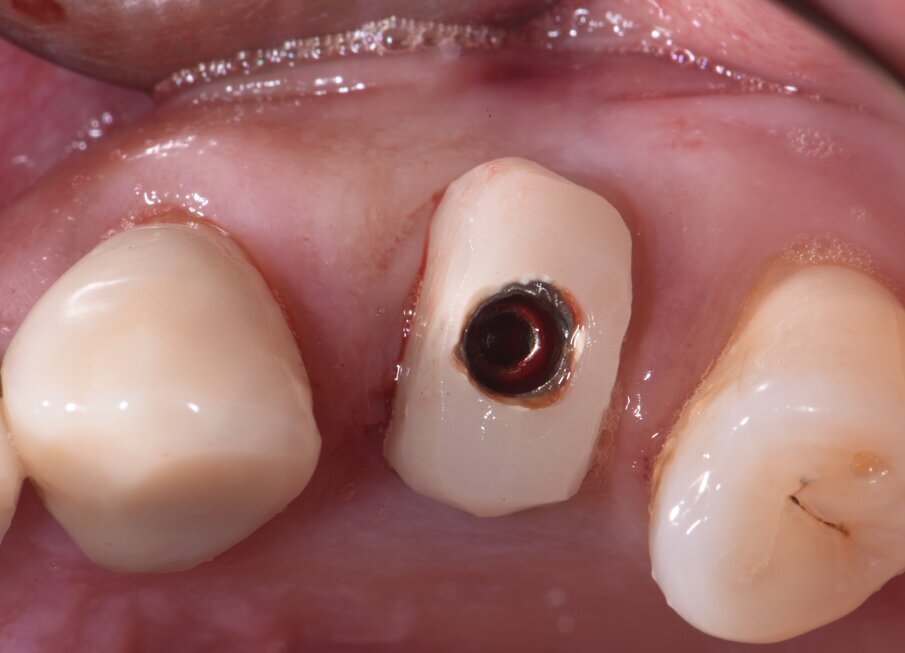

Per ridurre la perdita volumetrica dei tessuti perimplantari, alcuni studi clinici5-7 hanno riportato l’utilizzo delle cappette di guarigione customizzate avvitate sugli impianti immediatamente inseriti negli alveoli post-estrattivi. In questo case report viene descritta l’applicazione delle cappette di guarigione customizzate seguendo la procedure Cad-Cam in un flusso di lavoro digitale. Prima di eseguire l’estrazione si procede con il rilevamento dell’impronta digitale per copiare l’anatomia del profilo d’emergenza del dente. A questo punto si estrae in modo molto conservativo il dente. Si posiziona l’impianto dentale senza inserimento dei biomateriali nel void creato fra la superficie dell’impianto e la parete dell’alveolo. Si avvita una cappetta eseguita con la procedura Cad-Cam copiando l’anatomia del dente estratto (Figg. 1a, 2).

Fig. 2 - Coppetta di guarigione castomizzata avvitata sull’impianto appena inserito nell’alveolo post-estrattivo.